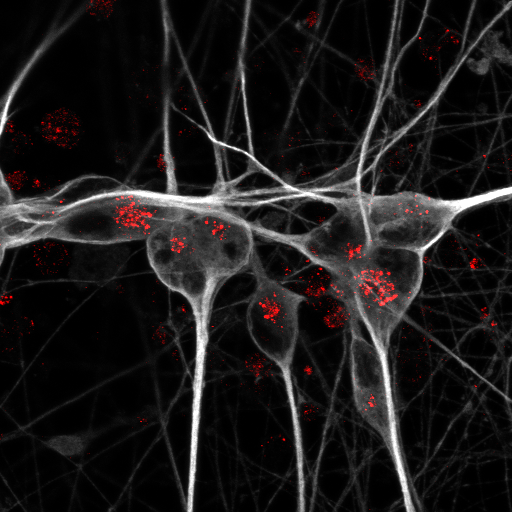

Detection of apoE receptor sortilin (red) in iPSC-derived human neurons (grey).

Detection of apoE receptor sortilin (red) in iPSC-derived human neurons (grey). Photo: Anna K Greda, Universität Aarhus